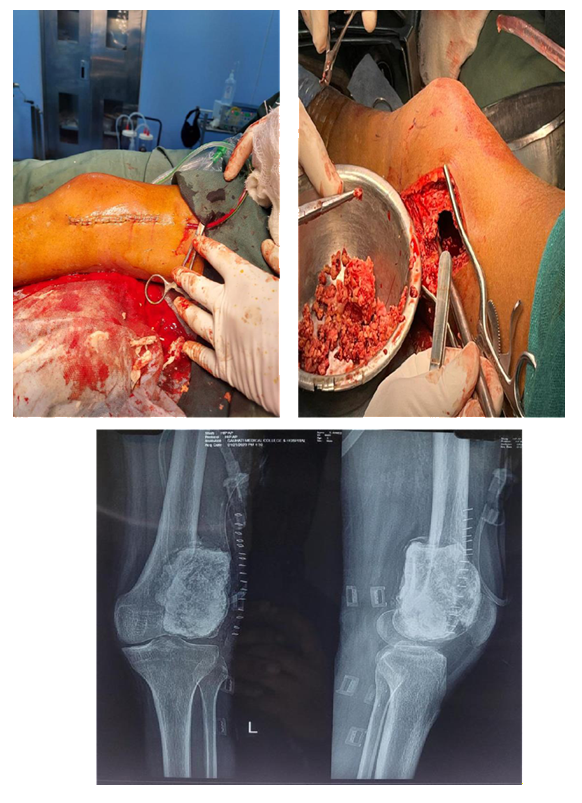

Intraoperative

Post Operative